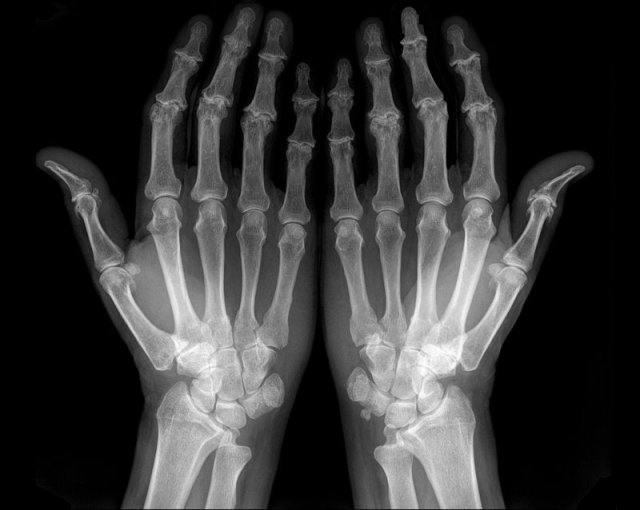

SLE: Z-thumbs and swan neck fingers SLE: Z-thumbs and swan neck fingers

Z-thumbs and swan neck fingers in a patient with SLE.

The deformities are thought to be a consequence of low-grade inflammation of the synovial membrane and capsule resulting in ligamentous laxity and muscular contracture.

Swan neck deformity

Here another example with extensive alignment deformities without erosions or signs of cartilage damage in a patient with SLE.